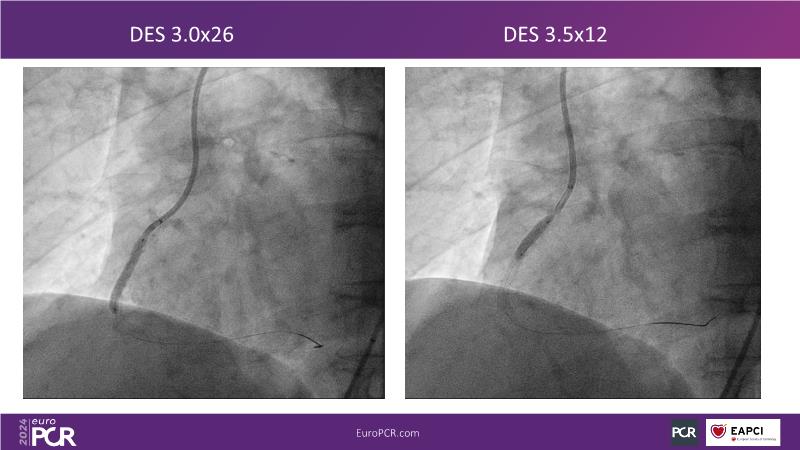

Follow this session to learn about the novel HC-IVL system, its application for moderate to severe calcified lesions, and procedural tips. The LithiX Hertz Contact IVL addresses unmet needs in coronary artery calcification by offering a simplified workflow with fewer devices and effective treatment for difficult lesions. Its novel design ensures safety and efficacy, with the PINNACLE I study's primary outcomes expected to confirm its effectiveness.